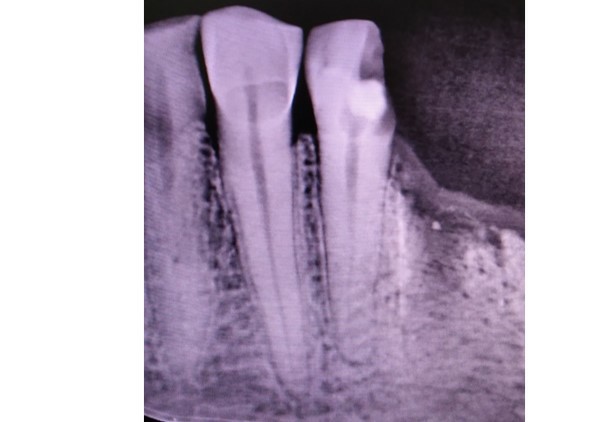

Before After

Before

After

Complex endodontic case